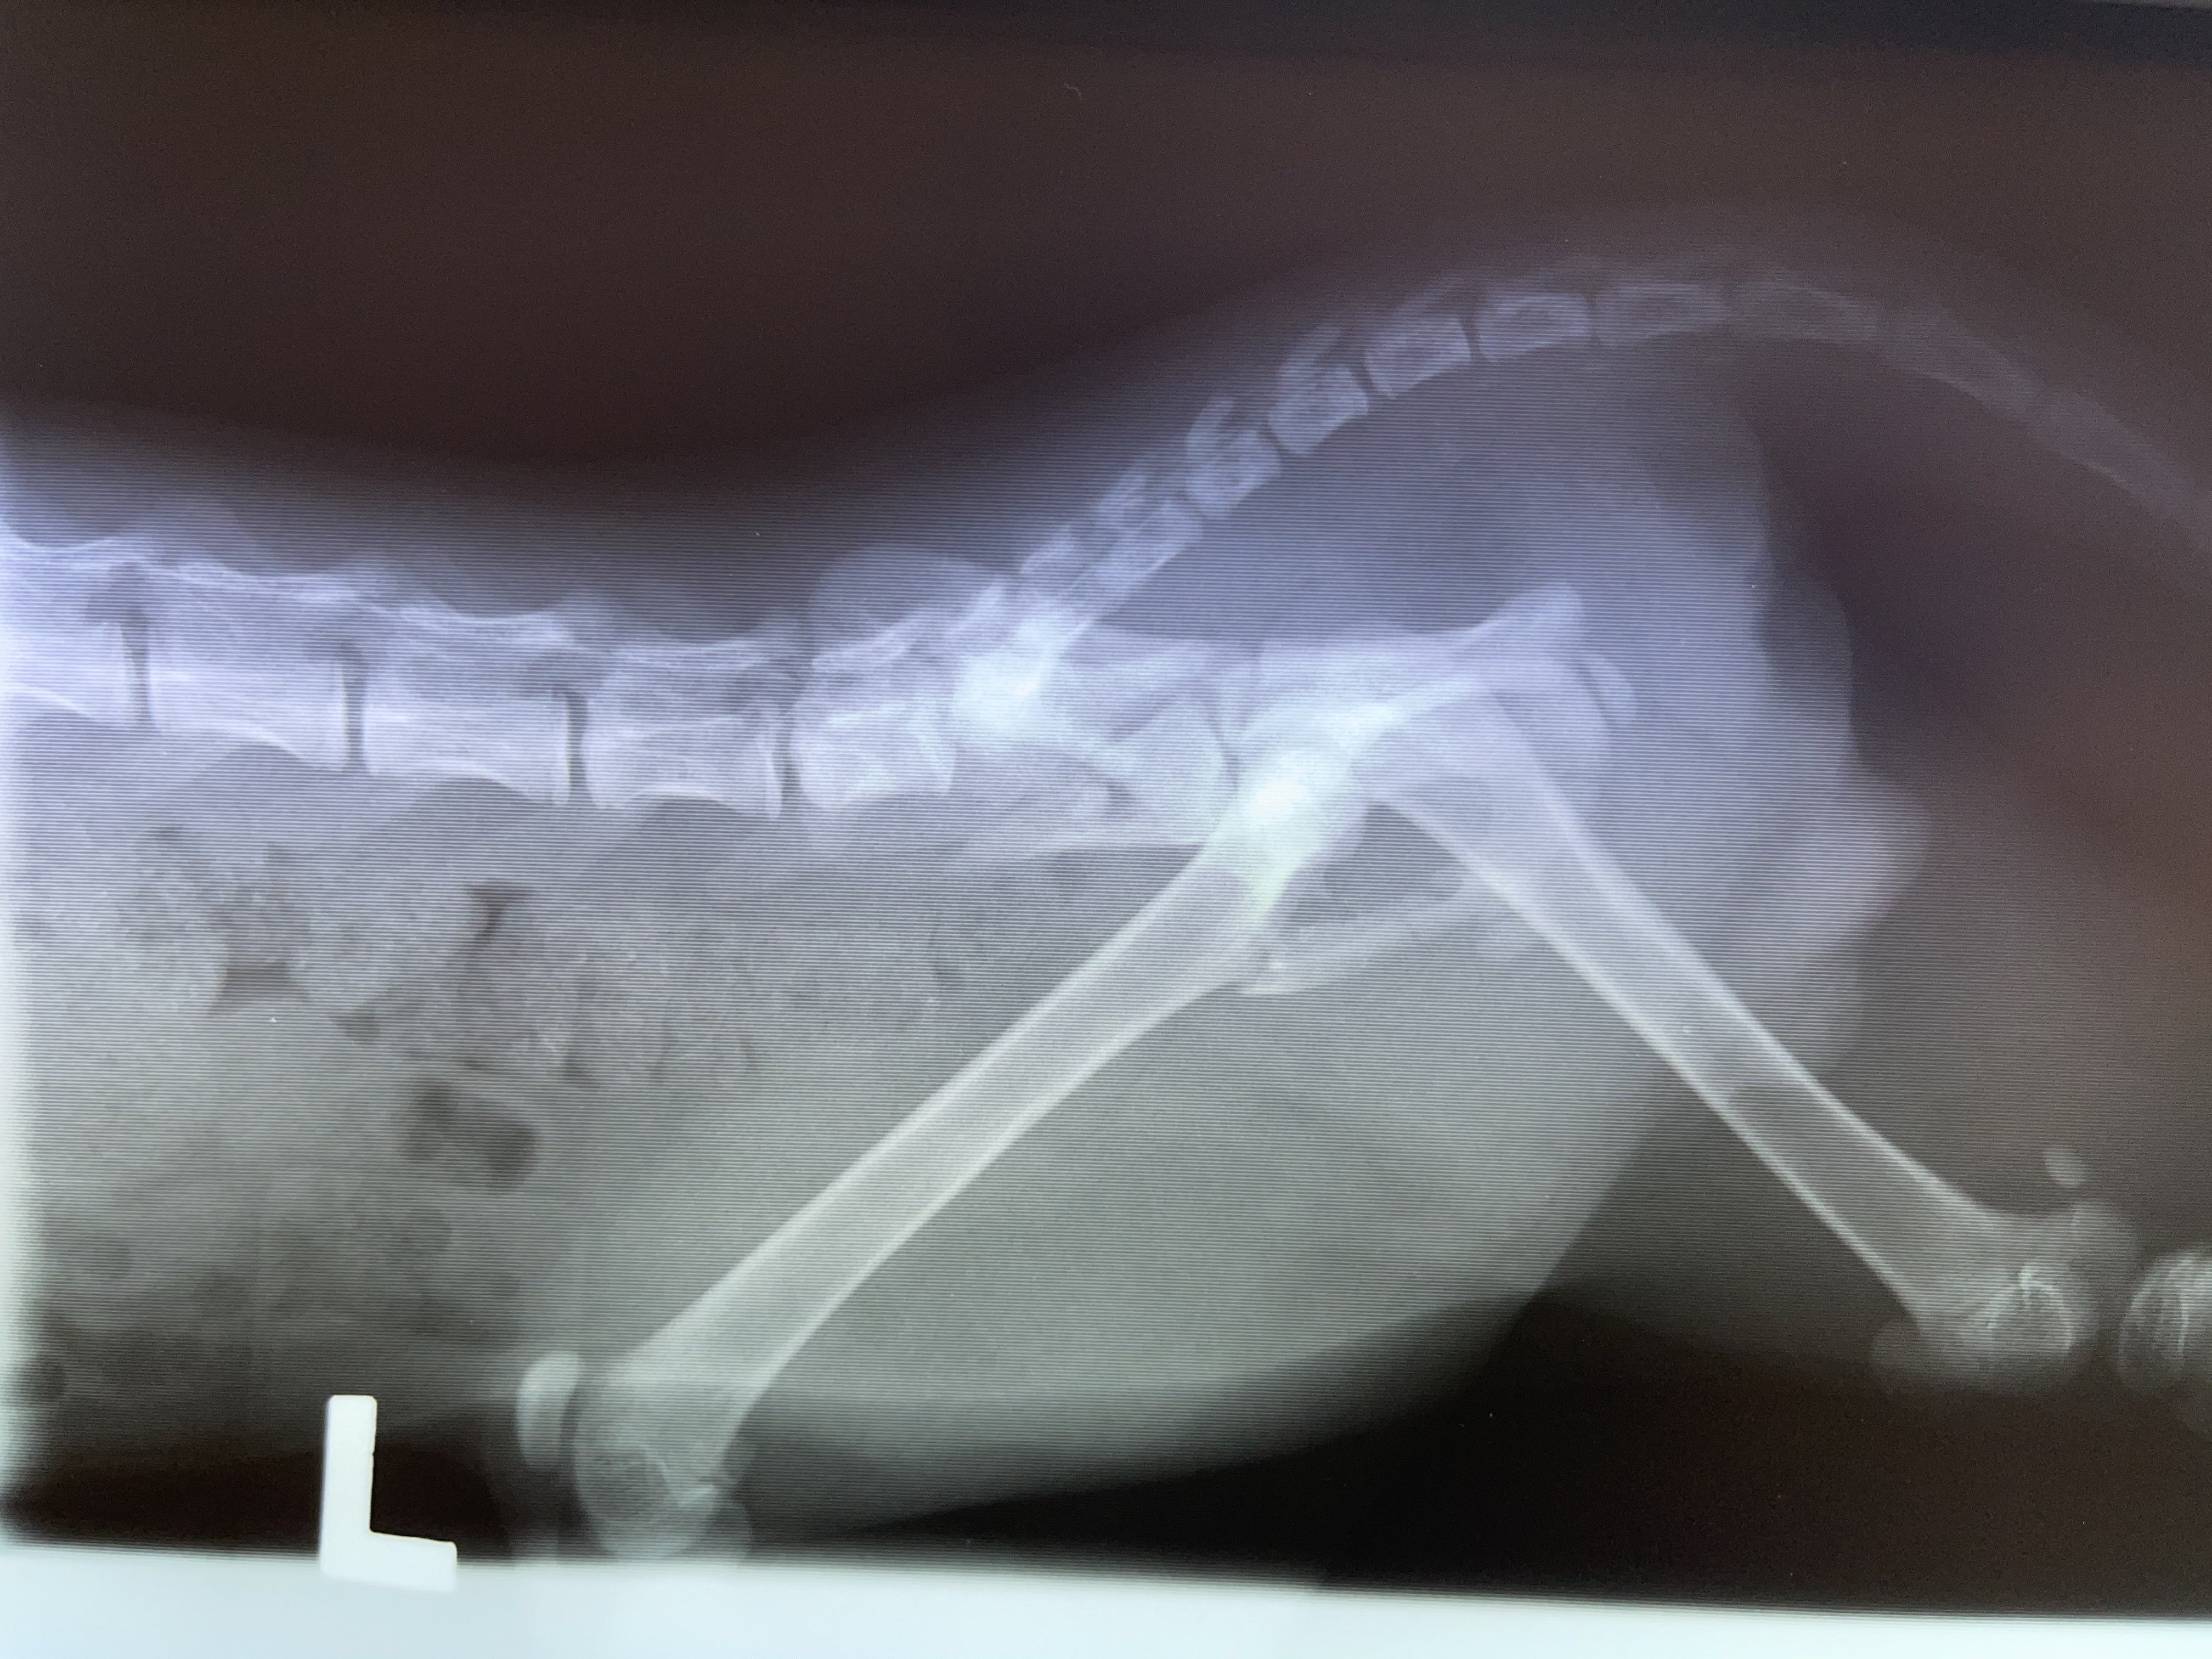

骨盤のレントゲン

検査費/入院費 合計:33,440円

<手術前>

手術前